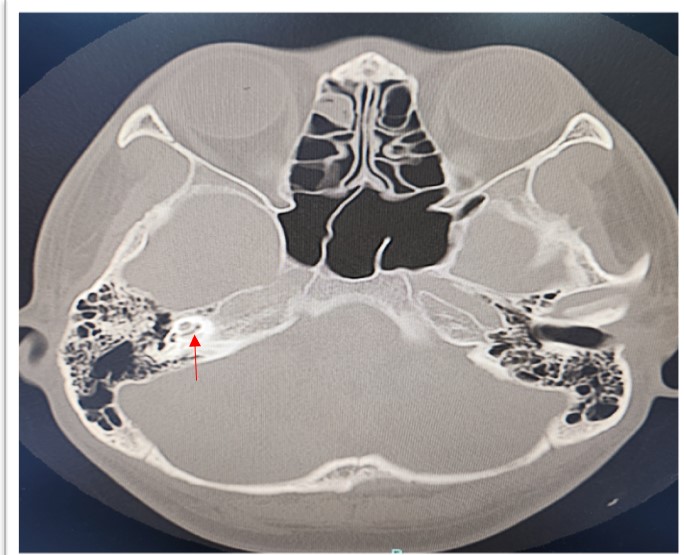

Coronavirus disease 2019 is a highly infectious disease. The complications of the disease markedly reduced after the introduction of vaccine. Thus, vaccination for COVID-19 is important and has been prompted in many countries. Reports on rare serious adverse events after COVID-19 vaccinations are well documented. The audio vestibular adverse event after COVID-19 vaccination have been reported. We herein discussed a case of labyrinthitis ossificans post COVID vaccination. A 23-year-old male presented with sudden onset right hearing loss (SNHL) with tinnitus 3 days after received COVID-19 vaccine. Pure Tone Audiometry (PTA) revealed right profound hearing loss with normal left hearing. High Resolution Computed Tomography (HRCT) of the temporal bone showed hyperdensity seen at the basal turn of the right cochlea, with Magnetic Resonance Imaging (MRI) revealed focal loss of normal T2-weighted hyperintense signal intensity of the scala tympani of the basal turn of the cochlear, suggestive of labyrinthitis ossificans. He was fitted with hearing aid and undergone for right cochlear implant for hearing rehabilitation. Labyrinthitis ossificans is commonly caused by infection and inflammation, and less commonly trauma, tumors, hemorrhage, or autoimmune inner ear disease. The correlation with vaccination is yet to be revealed and required further study.

Penyakit koronavirus 2019 (COVID-19) adalah penyakit yang sangat berjangkit. Komplikasi penyakit ini berkurangan dengan ketara selepas pengenalan vaksin. Oleh itu, vaksinasi untuk COVID-19 adalah penting dan telah digalakkan di banyak negara. Laporan mengenai kesan sampingan serius yang jarang berlaku telah didokumenkan dengan baik. Kesan otologi selepas vaksinasi COVID-19 yang secara tiba-tiba kehilangan pendengaran sensorineural (SNHL) belah kanan juga dilaporkan. Kami membincangkan kes labyrinthitis ossificans selepas vaksinasi COVID. Seorang lelaki berusia 23 tahun mengalami kehilangan pendengaran sebelah kanan secara tiba-tiba dengan kesan gigitan 3 hari selepas menerima vaksin COVID-19. Audiometri Nada Tulen (PTA) menunjukkan kehilangan pendengaran dalam yang ketara pada sebelah kanan dengan pendengaran sebelah kiri yang normal. Tomografi Berkomputer Resolusi Tinggi (HRCT) pada tulang temporal menunjukkan hiperdensiti yang dilihat pada selekoh basal koklea kanan, dengan Pengimejan Resonans Magnetik (MRI) menunjukkan kehilangan fokus intensiti isyarat hiperintens berwajaran T2 normal bagi tympani scala selekoh koklear, yang mencadangkan labyrinthitis ossificans. Beliau dipasangkan dengan alat bantu pendengaran dan menjalani implan koklear kanan untuk pemulihan pendengaran. Labyrinthitis ossificans biasanya disebabkan oleh jangkitan dan keradangan, dan jarang disebabkan oleh trauma, tumor, pendarahan, halangan vaskular arteri labirinthine, pembedahan atau penyakit telinga dalam autoimun. Hubungan dengan vaksinasi masih belum didedahkan dan memerlukan kajian lanjut.